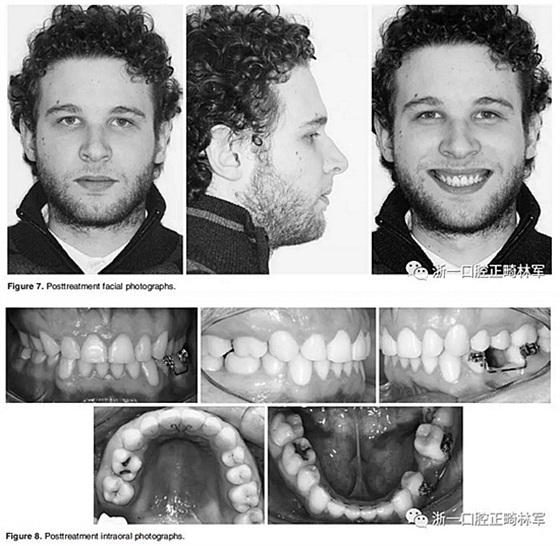

在治療結(jié)束時,面部基本對稱(Figure 7)。上中線與面中線重合,下中線向左偏0.5mm,傾斜的合平面得到矯正,獲得了良好的咬合關(guān)系,具有正常的覆合和覆蓋,留下7mm的空間用于植入左下前磨牙(Figure 8、9)。

全景片顯示牙根平行度良好、無吸收。此外,在左下第二前磨牙的區(qū)域獲得了用于植入種植體修復的良好空間。頭顱側(cè)位片和疊加顯示,上下切牙傾斜度以及前后和垂直向位置的變化也很大(Figure 10、11; Table 1)。